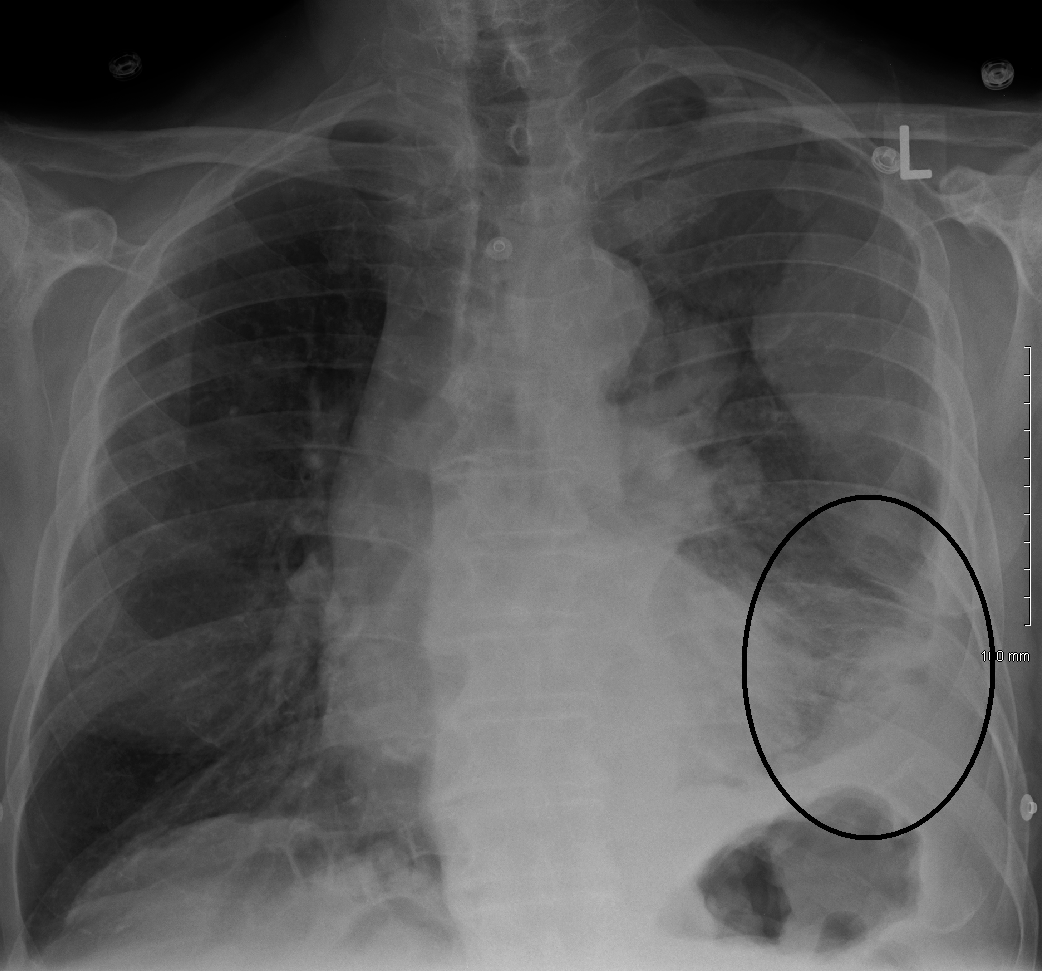

중피종을 보여주는 흉부 X선 사진

중피종 진단은 증상이 여러 다른 질환과 유사하기 때문에 어려운 경우가 많다. 진단은 환자의 병력 검토부터 시작하며, 석면 노출 병력은 중피종에 대한 임상적 의심을 높일 수 있다. 신체 검사 후 흉부 X선 촬영과 폐 기능 검사를 할 수 있다. X선 촬영에서 석면 노출 후 흔히 나타나는 흉막 비후가 나타나면 중피종에 대한 의심이 증가한다.[15] CT 스캔 또는 MRI를 일반적으로 실시한다.

• 영상 소견: 대부분 X선 검사에서 흉막외 징후나 흉수 축적을 확인할 수 있다. 일반적으로 한쪽 폐에만 나타난다. 흉부 CT에서도 동일한 소견을 얻을 수 있다. FDG-PET에서는 종양의 양성 반응을 확인할 수 있다.